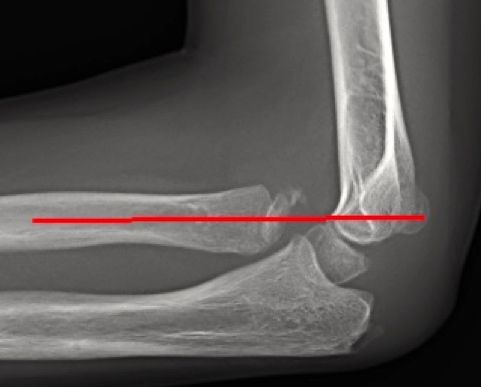

- El radio se dirige al capitelum en todas las proyecciones: cuando esto no ocurre, se debe sospechar una fractura del cóndilo lateral, una fractura del cuello del radio, una fractura-luxación de Monteggia o equivalente o una luxación de codo (Figura 4).